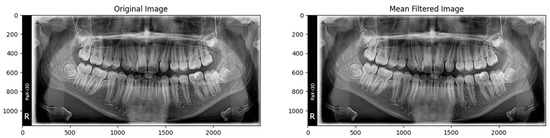

2.3.1. Reading Images

2.3.2. Preprocessing Step

2.3.3. Augmentation Step